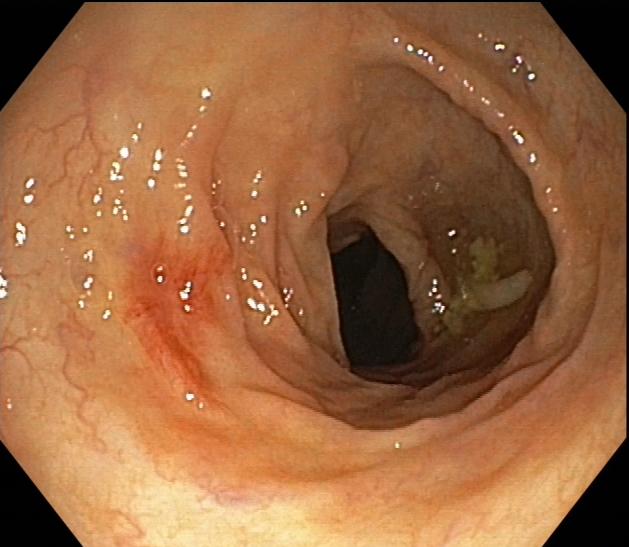

●肠镜检查示:慢性乙状结肠;直肠黏膜炎;结肠蜘蛛痣;外痔。

肠镜显像1

2.皮肤粘膜未见肝掌、蜘蛛痣,结肠镜检可见蜘蛛痣。

肠道蜘蛛痣多见于门脉高压性肠病患者中,直肠、肛管静脉曲张,门脉高压性直肠静脉曲张往往引起下消化道出血;内镜下见多发性樱桃红病变,血管呈蜘蛛样血管扩张以及退行性改变;蜘蛛痣与肝肺综合征、酒精性肝病、肝炎肝硬化、门脉高压性胃肠病、食管胃静脉曲张破裂出血等都有相关性,我院曾收治过因肠道血管病变导致消化道出血的患者,所以临床上仍应高度警惕此类并发症,出现肠道蜘蛛痣时应根据病史、生化检查、影像、内镜等检查综合分析评估,动态观察,谨防出血。